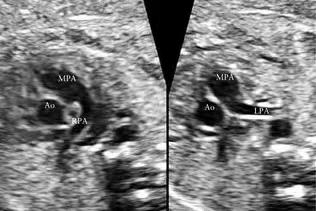

超声所见:胎儿的心脏位于左侧胸前内,四腔心切面、左右室流出道切面、主动脉弓及导管弓切面、下腔静脉及肺静脉均未见异常。但在三血管切面及心底短轴切面发现异常,左肺动脉起始于主肺动脉的右侧并向左侧走行,右肺动脉起始于主肺动脉左侧向右走行,主肺动脉及左右肺动脉内径均未见狭窄,血流未见异常。没有发现其他的心内畸形。

超声提示:胎儿左右肺动脉交叉

(胎儿肺动脉交叉 )

正常情况下,左、右肺动脉分别起自主肺动脉左、右两侧,然后进入左、右肺门。肺动脉交叉是一种非常罕见的肺动脉分支起源及走形异常的变异,左肺动脉起始于主肺动脉右侧,右肺动脉起始于主肺动脉左侧,两者交叉然后分别进入左、右肺门,标准心底短轴切面不能同时显示左、右肺动脉起始段。